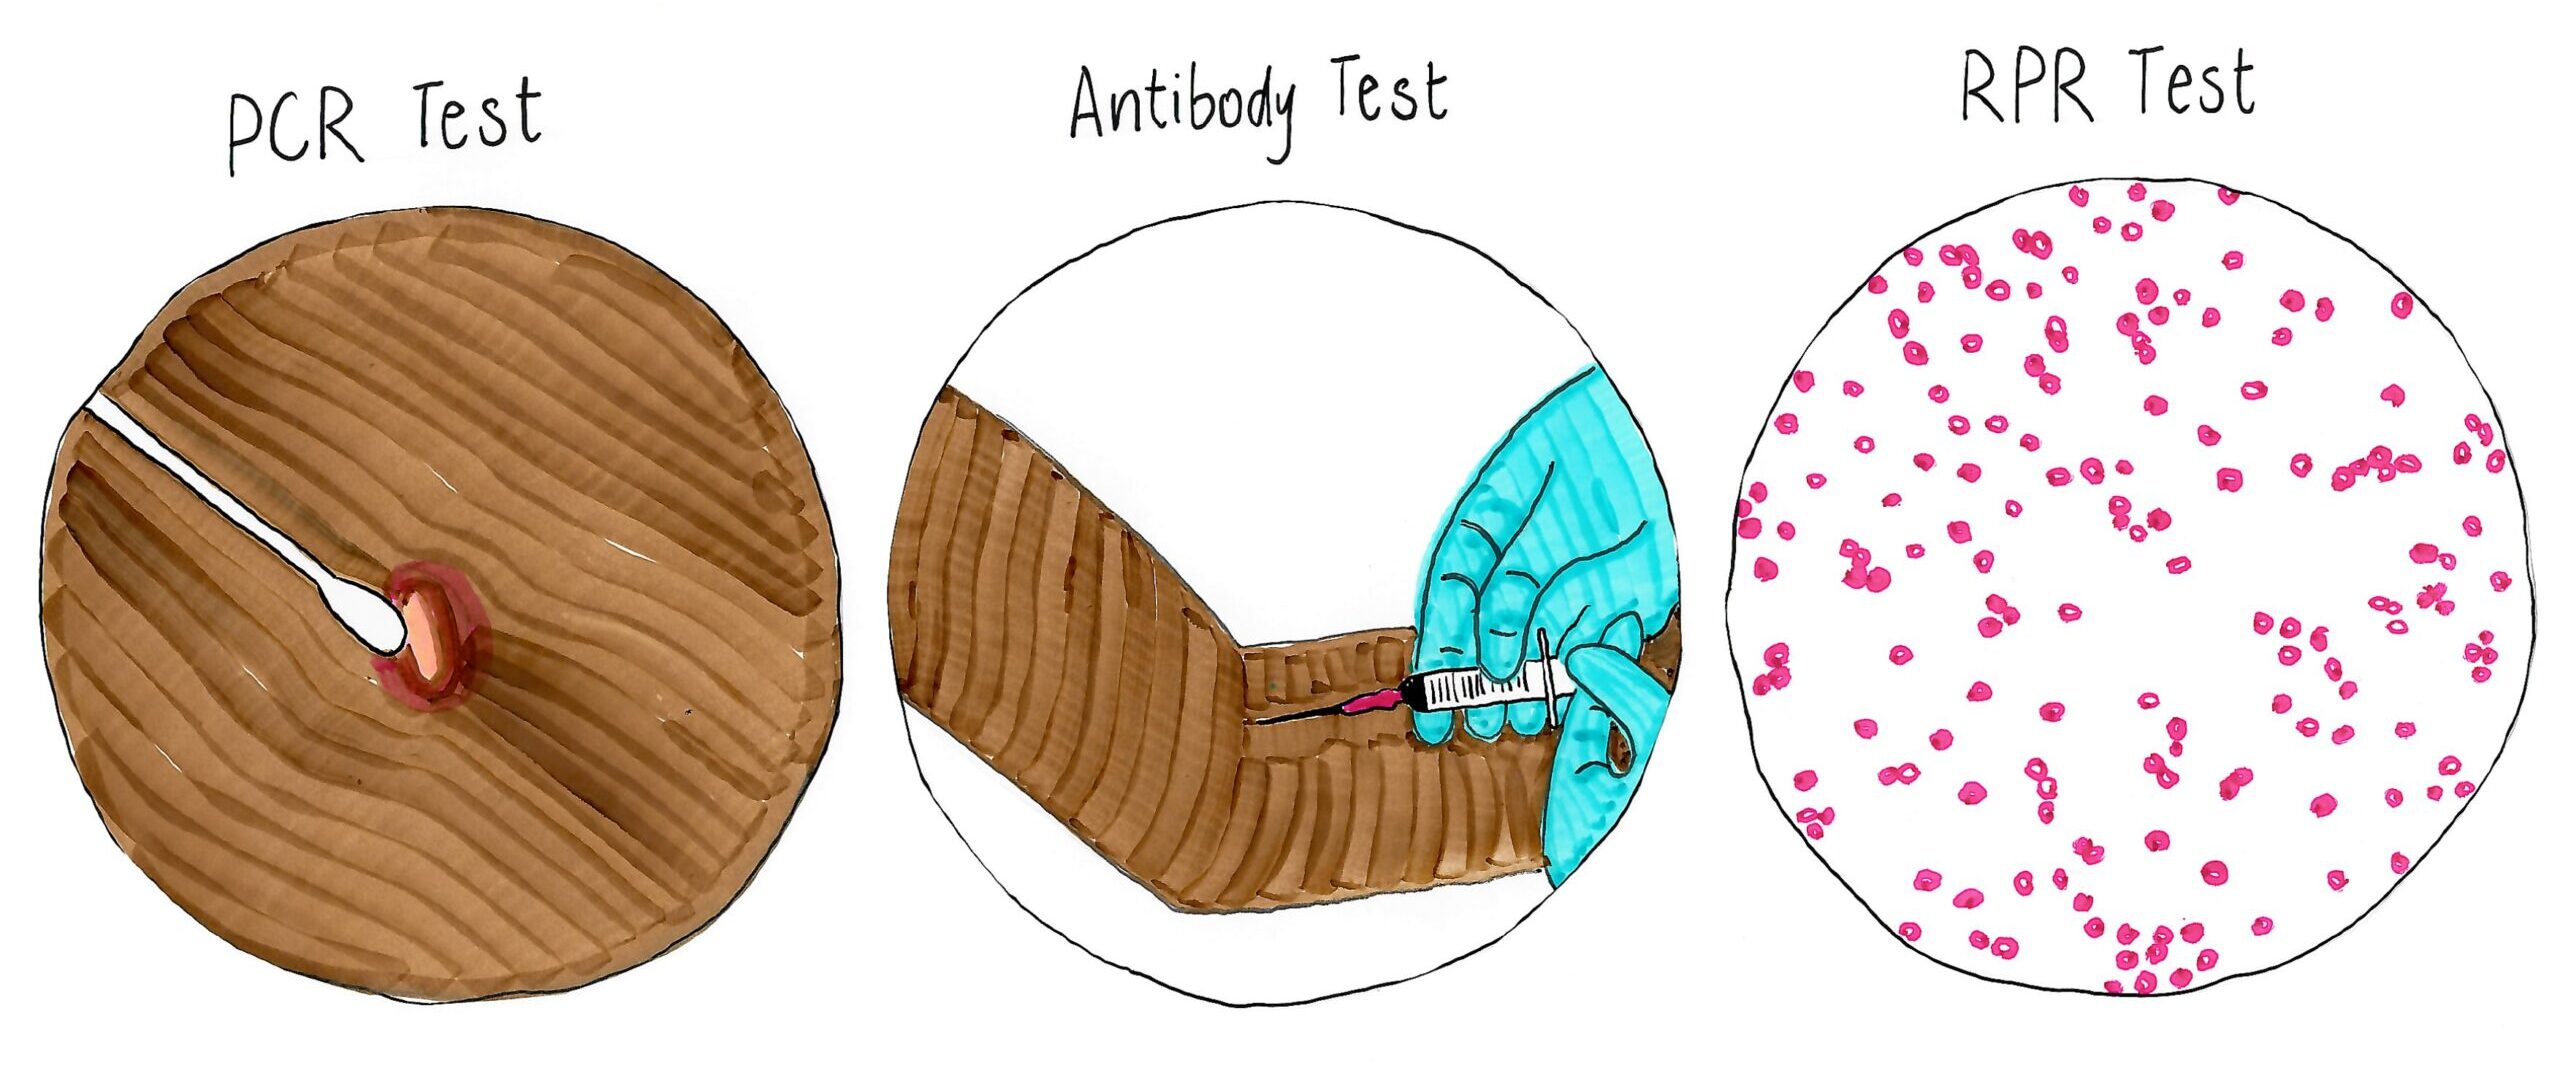

Testing

How to know which Syphilis test to ask for?

A doctor or clinic may not understand the different tests for Syphilis. The person who is requesting a test can ask what type of Syphilis test the doctor or clinic is going to do.

To request the type of test that is right for you, you will need to understand the different tests.

Antibody test

- Blood test.

- To see if the person has ever been exposed to Syphilis.

- This test will not detect what stage of Syphilis the person has.

If there is a reactive (positive) result, the blood sample is tested twice in the lab to be sure of the result.

Note: If someone has ever had Syphilis before, even if it was treated and is now inactive, Syphilis will still show up on the antibody test. In this case, the antibody test does not indicate a current case of Syphilis that needs treatment. Only the PCR or RPR tests (explained next) can confirm this.

Polymerase Chain Reaction test (PCR test)

- Skin swab of Primary Syphilis symptoms.

- This test will not detect what stage of Syphilis the person has.

- This test detects if the person has an active case of Syphilis.

Rapid Plasma Reagin test (RPR test)

- Blood test.

- This test detects if someone has an active case, AND what stage of Syphilis they have.

- This test is done in a lab, by hand.

- Treatment decisions are sometimes based on the RPR test.

If a person has ever had Syphilis before, and been treated, the RPR test is a method to detect if the person has been re-infected.

This is why it is very important to tell the clinic about previous Syphilis infections and treatment.

Point of Care Rapid Test for Syphilis

- Finger prick blood test.

- This test can only determine if you have ever been exposed to Syphilis. Point of Care Rapid Tests must be done in combination with traditional Syphilis blood testing to confirm that the infection is current.

- Point of Care Rapid Tests are available to priority populations, such as Aboriginal and Torres Strait Islander peoples, injecting drug users and men who have sex with men, at some sexual health clinics. Sex work status alone may not necessarily make you eligible for Point of Care Rapid testing for Syphilis.